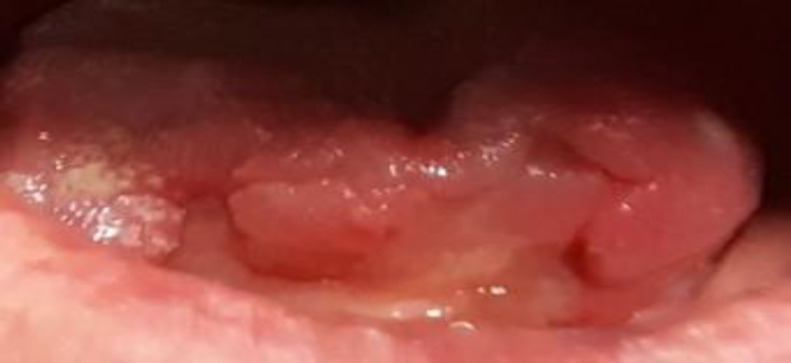

Case report: We present a case of a patient with bilateral necrosis of the anterior third of the tongue, occurring 3 years after chemoradiotherapy treatment for squamous cell carcinoma of the floor of the mouth. Contrast-enhanced CT scan showed multiple areas of stenosis concerning both external carotid arteries and their branches, and total opacification of lingual arteries. Conservative management was performed, with auto-amputation on the fifth day, which allowed healing by secondary intention.